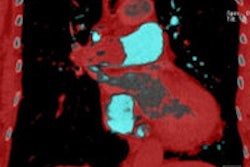

Pooled-blood volume (PBV) dual-energy CT (DECT) can be a powerful tool for separating clinically important pulmonary embolism (PE) from less important filling defects that won't impact the patient, explained researchers from St. George's Hospital in London. And while most multidetector-row CT scanners can evaluate filling defects, DECT goes a step further by suggesting the appropriate treatment for the defect at hand. Most physiologically impairing occlusive PE are associated with perfusion defects on PBV imaging, while nonimpairing pulmonary hypertension cases do not cause perfusion defects at PBV imaging, the group wrote in an article you'll find here.